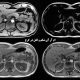

فیبرواسکن کبد در کرج یکی از روش های غیر تهاجمی در پزشکی بوده که با استفاده از دستگاه سونوگرافی و ام آر آی، میزان سفتی بافت کبد را بررسی می کنند.

در فیبرواسکن کبد با استفاده از پالس های ارتعاشی، میزان چربی و سفت بودن بافت کبد بررسی شده و بیماری های کبد چرب، هپاتیت B و C، فیبروز و سیروز کبدی قابل تشخیص هستند.

فیبرواسکن کبد در کرج به کمک دستگاه سونوگرافی و ام آر آی، اطلاعات دقیقی از میزان چربی کبد و سفت بودن بافت کبد در اختیار پزشک قرار می دهد.

پزشک با کمک نتایج بدست آمده بیماری های: کبد چرب، هپاتیت، فیبروز و سیروز کبدی را تشخیص داده و درمان مناسب را شروع می کند.